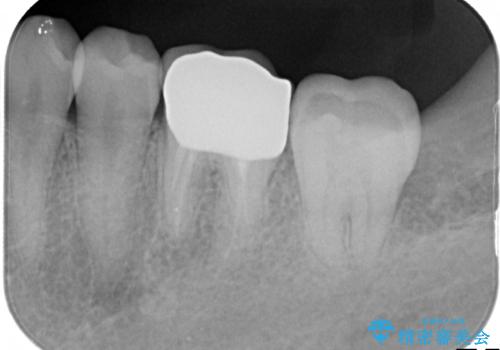

- 下の奥歯の銀歯を白くしたいとのことで来院されました。

痛みなどの症状はなく、前に根管治療を行っている歯になります。

古い銀歯を除去し、審美性の良いセラミッククラウンでの治療を行うこととしました。

銀歯を除去し、セラミッククラウンに替えました。

審美性が良くなるだけでなく、拡大鏡を使用した治療、精度の高い材料の使用によって、虫歯の再発リスクを減らすことができます。